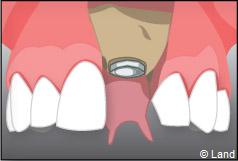

À l’issue de sa mise en place chirurgicale, une bague de cicatrisation en titane peut être directement vissée sur l’implant. Ainsi une seconde chirurgie ne sera pas nécessaire pour découvrir l’implant.

La technique en une seule étape chirurgicale n’est pas toujours possible, c’est à votre chirurgien-dentiste de prendre la décision.

Pour finir, une prothèse sera mise sur cet implant qui se comportera comme une racine artificielle.